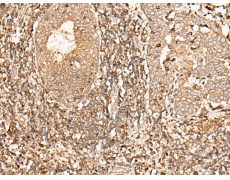

IHC positive control: |

Human esophagus cancer |